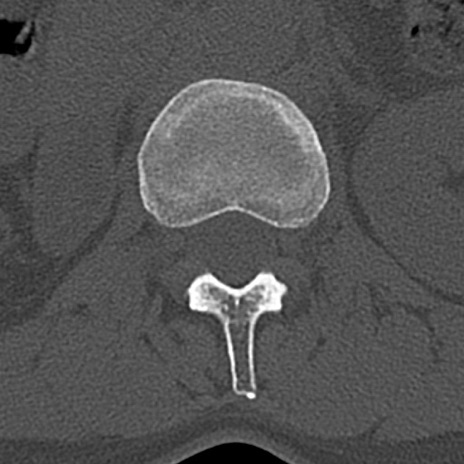

【整形】TIPS症例4 腰椎CT(横断像)

腰椎CT

横断像と矢状断像